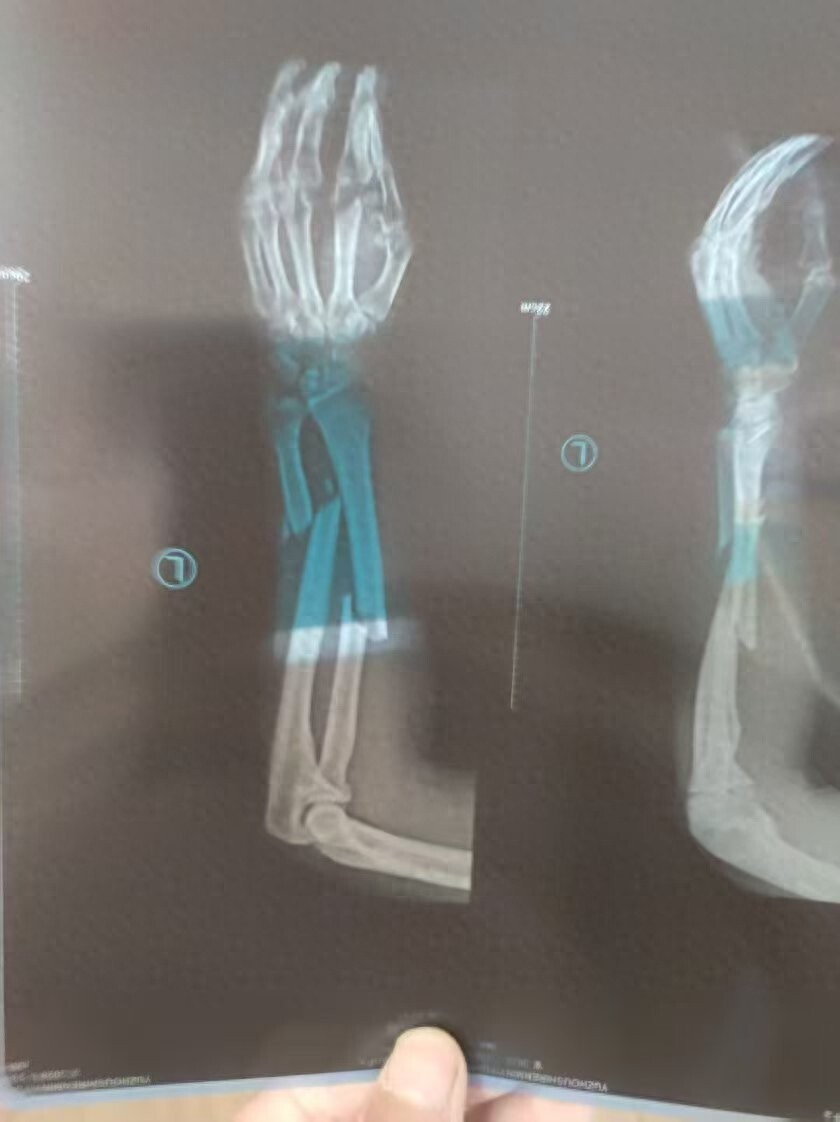

河南男子王先生在煤矿巷道中打钻施工时胳膊被钻机拧断,被鉴定为八级伤残,劳动仲裁认定企业需支付王先生工伤补助金37万余元,煤矿却迟迟不支付,法院查封了等值的800吨煤,却在拍卖前被矿上卖掉了。10月16日,华商报大风新闻以《大风追踪 | “男子被钻机拧断胳膊,难获37万工伤补助金”:法院查封的800吨煤,拍卖前被矿方私售》为题对此事进行了报道,引起当地相关部门和涉事单位的重视。